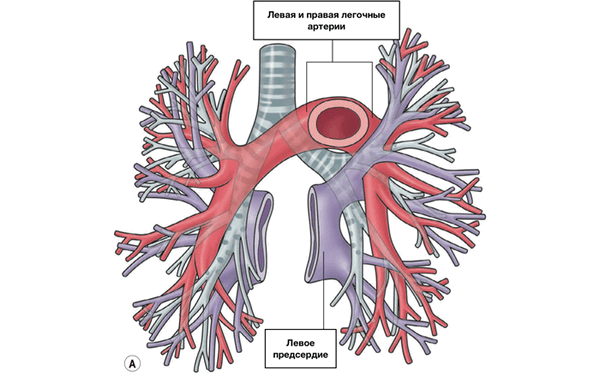

Сосуды легких

Легочный ствол (truncus pulmonalis) диаметром 30 мм выходит из правого желудочка сердца, от которого он отграничен своим клапаном. Начало легочного ствола и соответственно его отверстие проецируются на переднюю грудную стенку над местом прикрепления хряща III левого ребра к грудине. Легочный ствол расположен кпереди от остальных крупных сосудов основания сердца (аорты и верхней полой вены). Справа и позади него находится восходящая часть аорты, а слева прилежит левое ушко сердца. Легочный ствол, находящийся в перикардиальной полости, направляется впереди аорты влево и кзади и на уровне IV грудного позвонка (хряща II левого ребра) делится на правую и левую легочные артерии. Это место называется бифуркацией легочного ствола (bifurcаtio tninci pulmonalis). Между бифуркацией легочного ствола и дугой аорты расположена короткая артериальная связка(ligamentum arteriosum), представляющая собой заросший артериальный (боталлов) проток (ductus arteriosus).

Левая легочная артерия (a.pulmonаlis sinistra) короче и тоньше правой, проходит от бифуркации легочного ствола по кратчайшему пути к воротам левого легкого в поперечном направлении впереди нисходящей части аорты и левого бронха. На своем пути артерия перекрещивает левый главный бронх, а в воротах легкого располагается над ним. Соответственно двум долям левого легкого легочная артерия делится на две ветви. Одна из них распадается на сегментарные ветви в пределах верхней доли, вторая — базальная часть — своими ветвями кровоснабжает сегменты нижней доли левого легкого.

Из капилляров легкого начинаются венулы, которые сливаются в более крупные вены и в каждом легком формируют по две легочные вены.

Из двух правых легочных вен больший диаметр имеет верхняя, так как по ней оттекает кровь от двух долей правого легкого (верхней и средней). Из двух левых легочных вен больший диаметр имеет нижняя вена. В воротах правого и левого легких легочные вены занимают их нижнюю часть. В задней верхней части корня правого легкого расположен главный правый бронх, кпереди и книзу от него — правая легочная артерия.

У левого легкого сверху находится легочная артерия, кзади и книзу от нее — левый главный бронх. У правого легкого легочные вены лежат ниже артерии, следуют почти горизонтально и на своем пути к сердцу располагаются позади верхней полой вены, правого предсердия и восходящей части аорты. Обе левые легочные вены, которые несколько короче правых, находятся под левым главным бронхом и направляются к сердцу также в поперечном направлении, кпереди от нисходящей части аорты. Правые и левые легочные вены, прободая перикард, впадают в левое предсердие (их конечные отделы покрыты эпикардом).